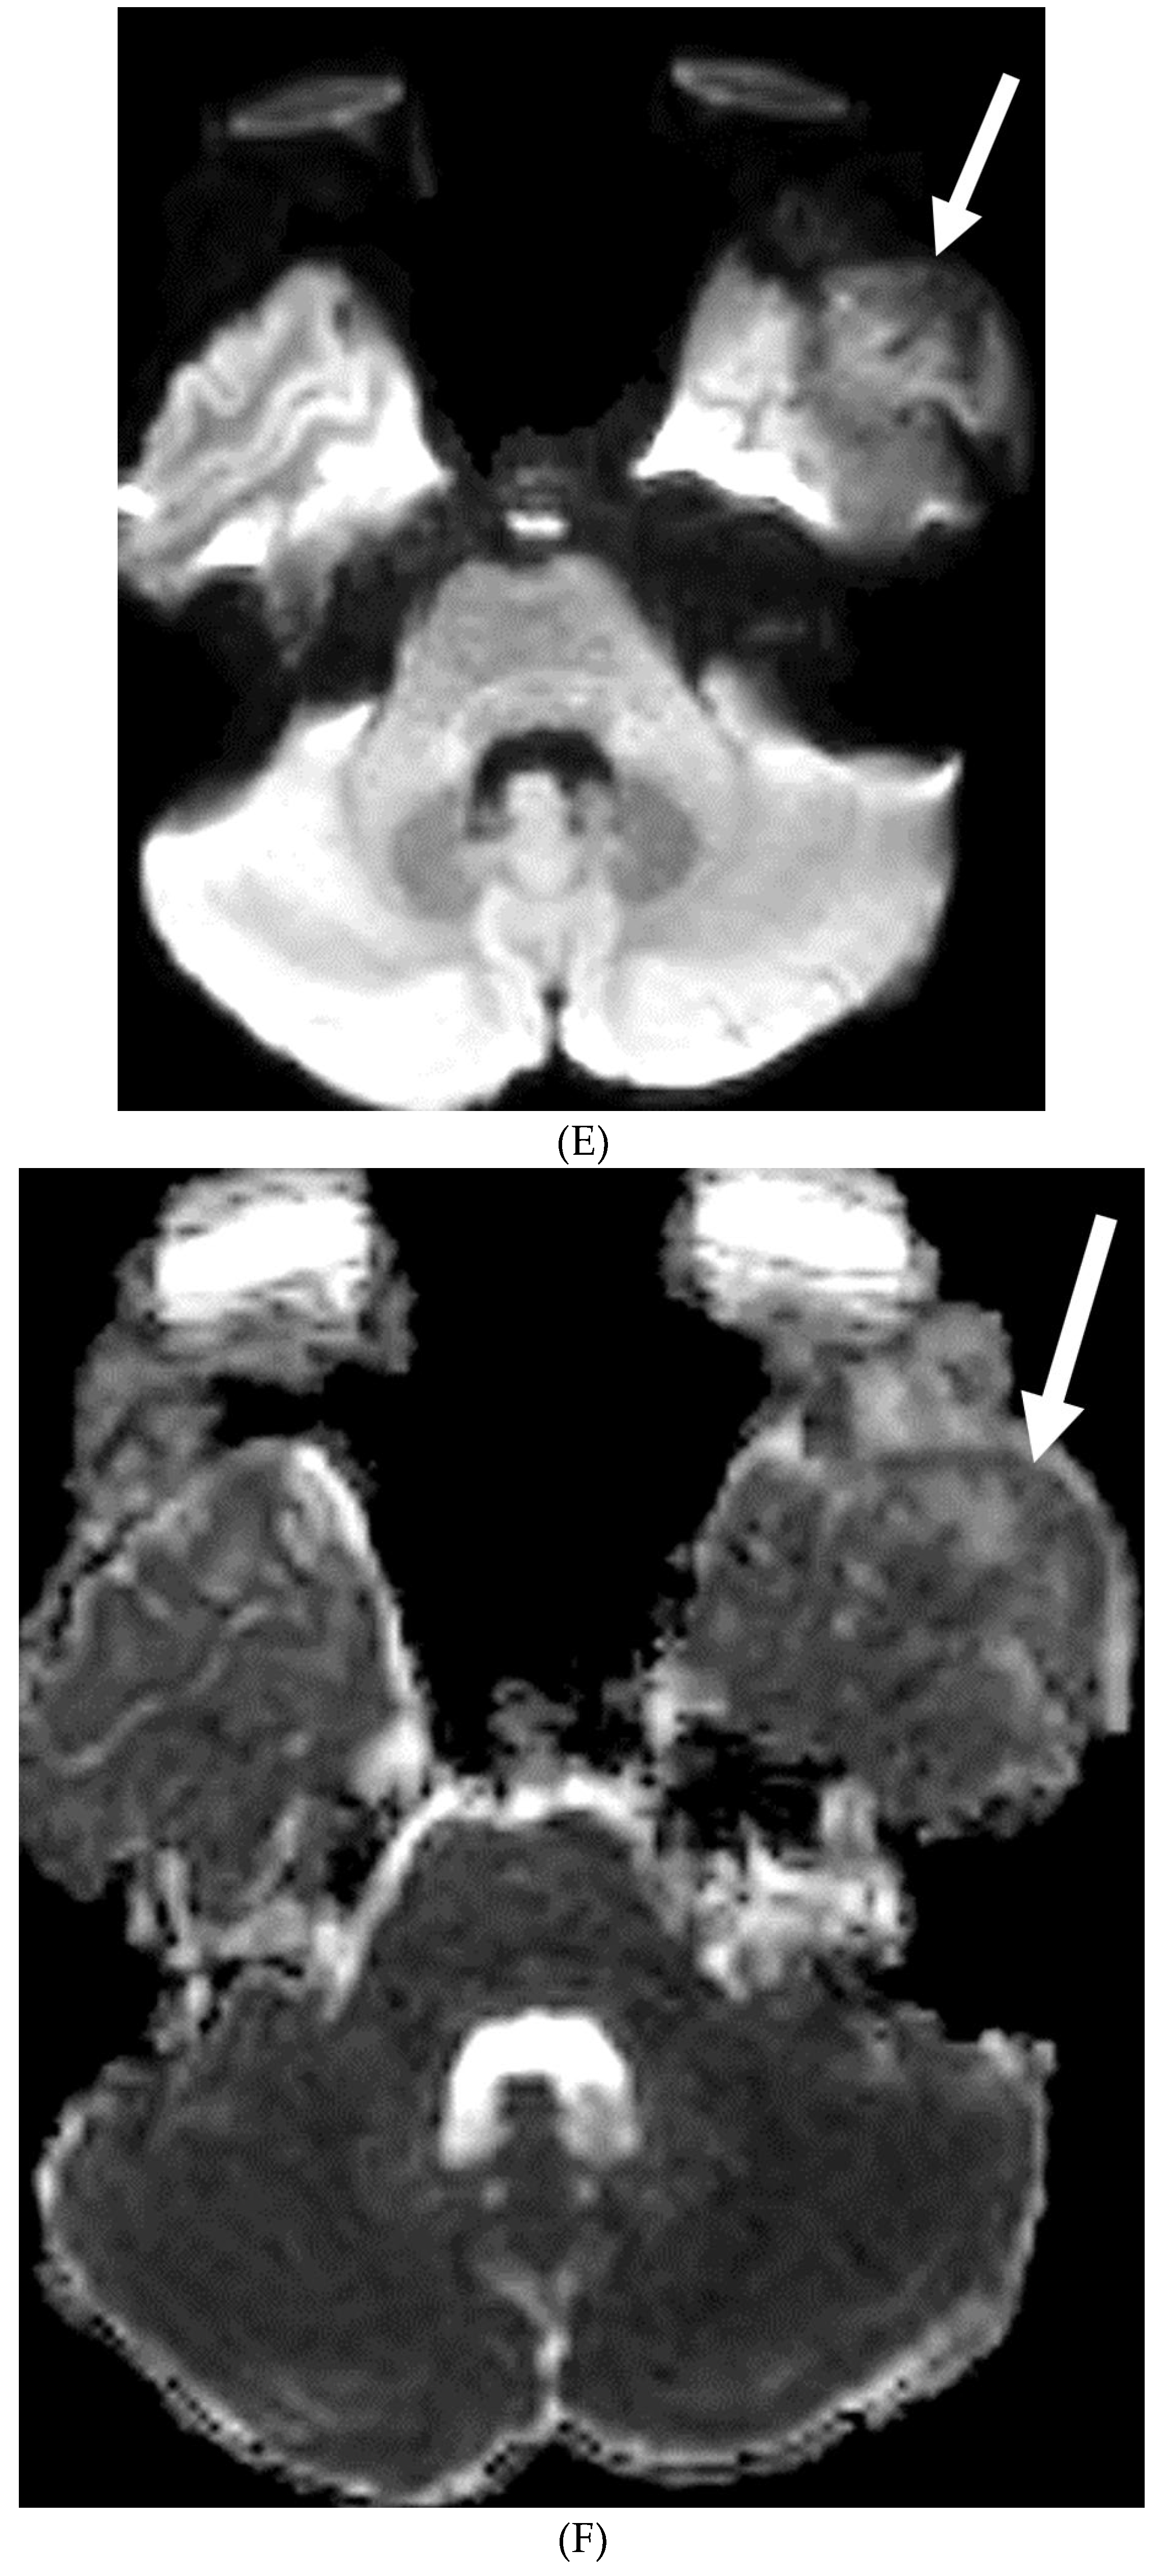

MOYA MOYA